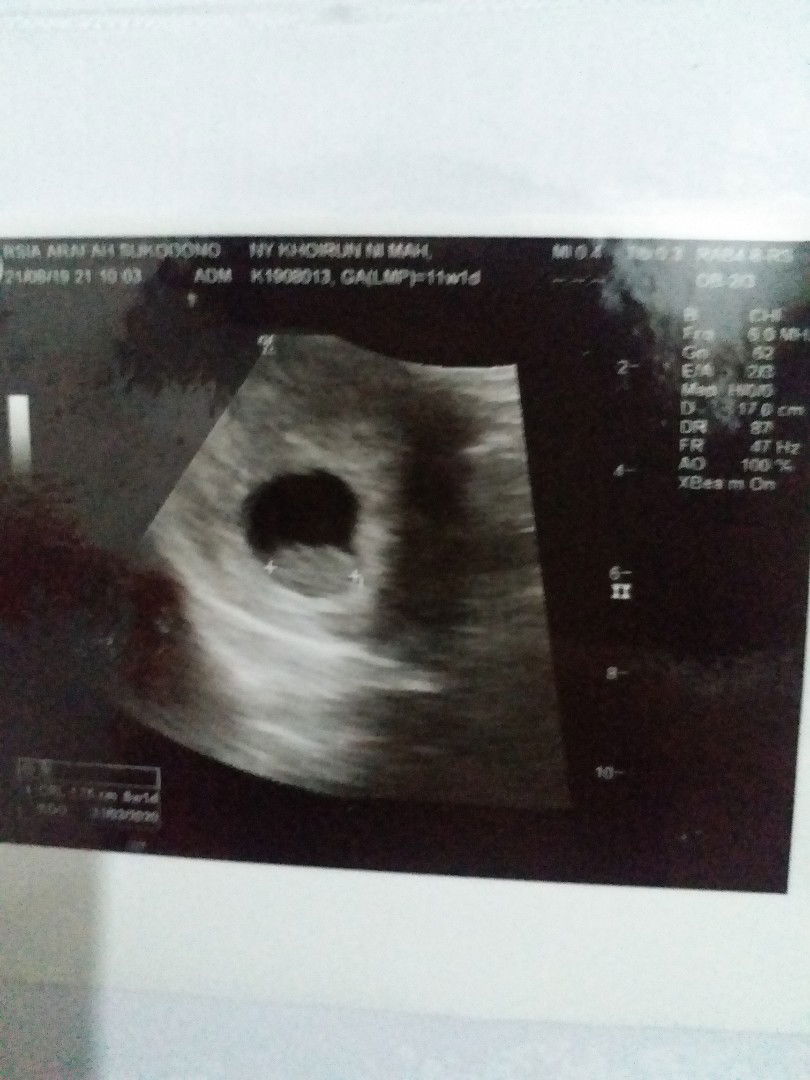

Hitungan HPL dan USG beda.

Hari pertama saya meanstruasi adalah selasa 4 Juni 2019, dan perhitungan HPL 11 Maret 2020 dengan usia kandungan sekarang 9w4d. Tetapi td saat USG dokter mengatakan bahwa usia kandungan saya masih 5w4d, bunda2 ada yg tau kenapa dan pernahkah mengalami seperti saya bunda. Trima kasih, mohon jawab yg bisa mengerti.